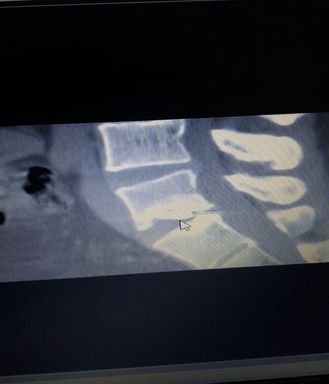

Mehmet Akdemir, Kayseri'de bulunan özel bir hastanede 17 Şubat 2015 tarihinde bel fıtığı ameliyatı oldu. Akdemir bir gün sonra kendisini ameliyat eden doktor tarafından "Fıtık temizlendiği sırada omurilik ve bel bölgesi arasında karga burun ucu denilen neşter kaldı. Çıkartılması büyük riskler taşıdığı için alınamadı" denilerek taburcu edildiğini iddia etti.

Akdemir "Doktora 'neden almadınız' diye sordum. O da bana 'O pozisyonda çok büyük risk vardı, ondan almadık' dedi. Neşter, röntgenlerde de açık şekilde belli oluyor. Bana İzmir'de bir İstanbul'da da üç profesörün bu ameliyatı yapabileceği söylendi. Çok büyük risk taşıdığı için maliyetli olacağı bilgisini de aldık" dedi.